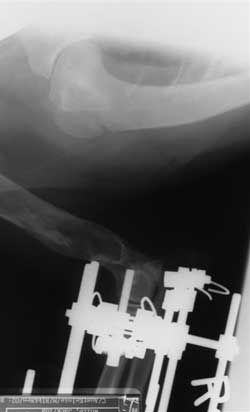

Hinged Ilizarov External Ring

Fixator

On December 03, 2002, attending Orthopedic

Surgeon Dr. W. Daniel Mertens, Texas A&M University Veterinary

Medical Teaching Hospital, after a physical examination and

diagnostic tests, he recommended that Guy would be a good candidate

for surgical repair with an External Ring Fixator device to slowly

lengthen and straighten the leg.

The 15 degree external rotation of the

radius was acutely corrected during surgery and the External Ring

Fixator was attached.

It was our responsibility to turn the

nuts on the motor and on the hinges twice daily. The Fixator was

wrapped to ensure that Guy didn't catch it on anything.

Another view of the External Ring

Heavy gauge wire and pins were used to hold the

Fixator in place. Since Guy's right elbow was luxated, a wire was used

to hold the elbow in correct position. |

Ulna being held in place

A wire held the ulna in place. The wire was removed

on December 17, 2002.